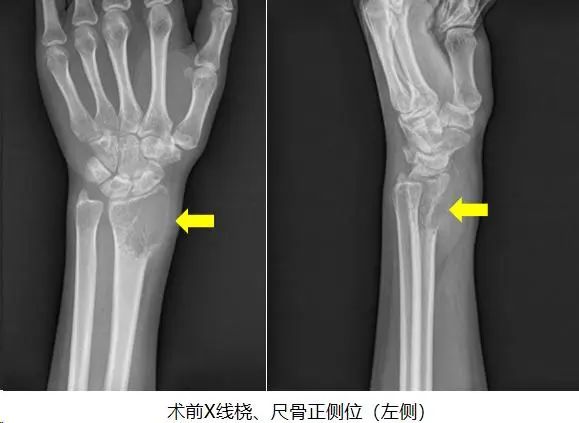

21岁的小英,一个多月前突然感觉自己左腕关节出现间断性疼痛,初期以为是运动时不小心扭伤,随着时间推移,她发现左手腕处居然长了一个质硬的包块,并到医院拍片后,发现左侧桡骨远端膨胀溶骨性破坏。随后曾到广州某三甲医院就诊,经过多番打听和比较后,选择来到我院骨质疏松与骨病骨肿瘤科外科门诊找到郑鸿主任就诊。

结合影像学检查结果以及病理穿刺结果,可以明确诊断为左侧桡骨骨巨细胞瘤 III级,首选手术切除病灶;且具有侵袭性的III级,则需要彻底完整切除肿瘤以及行桡骨重建手术。